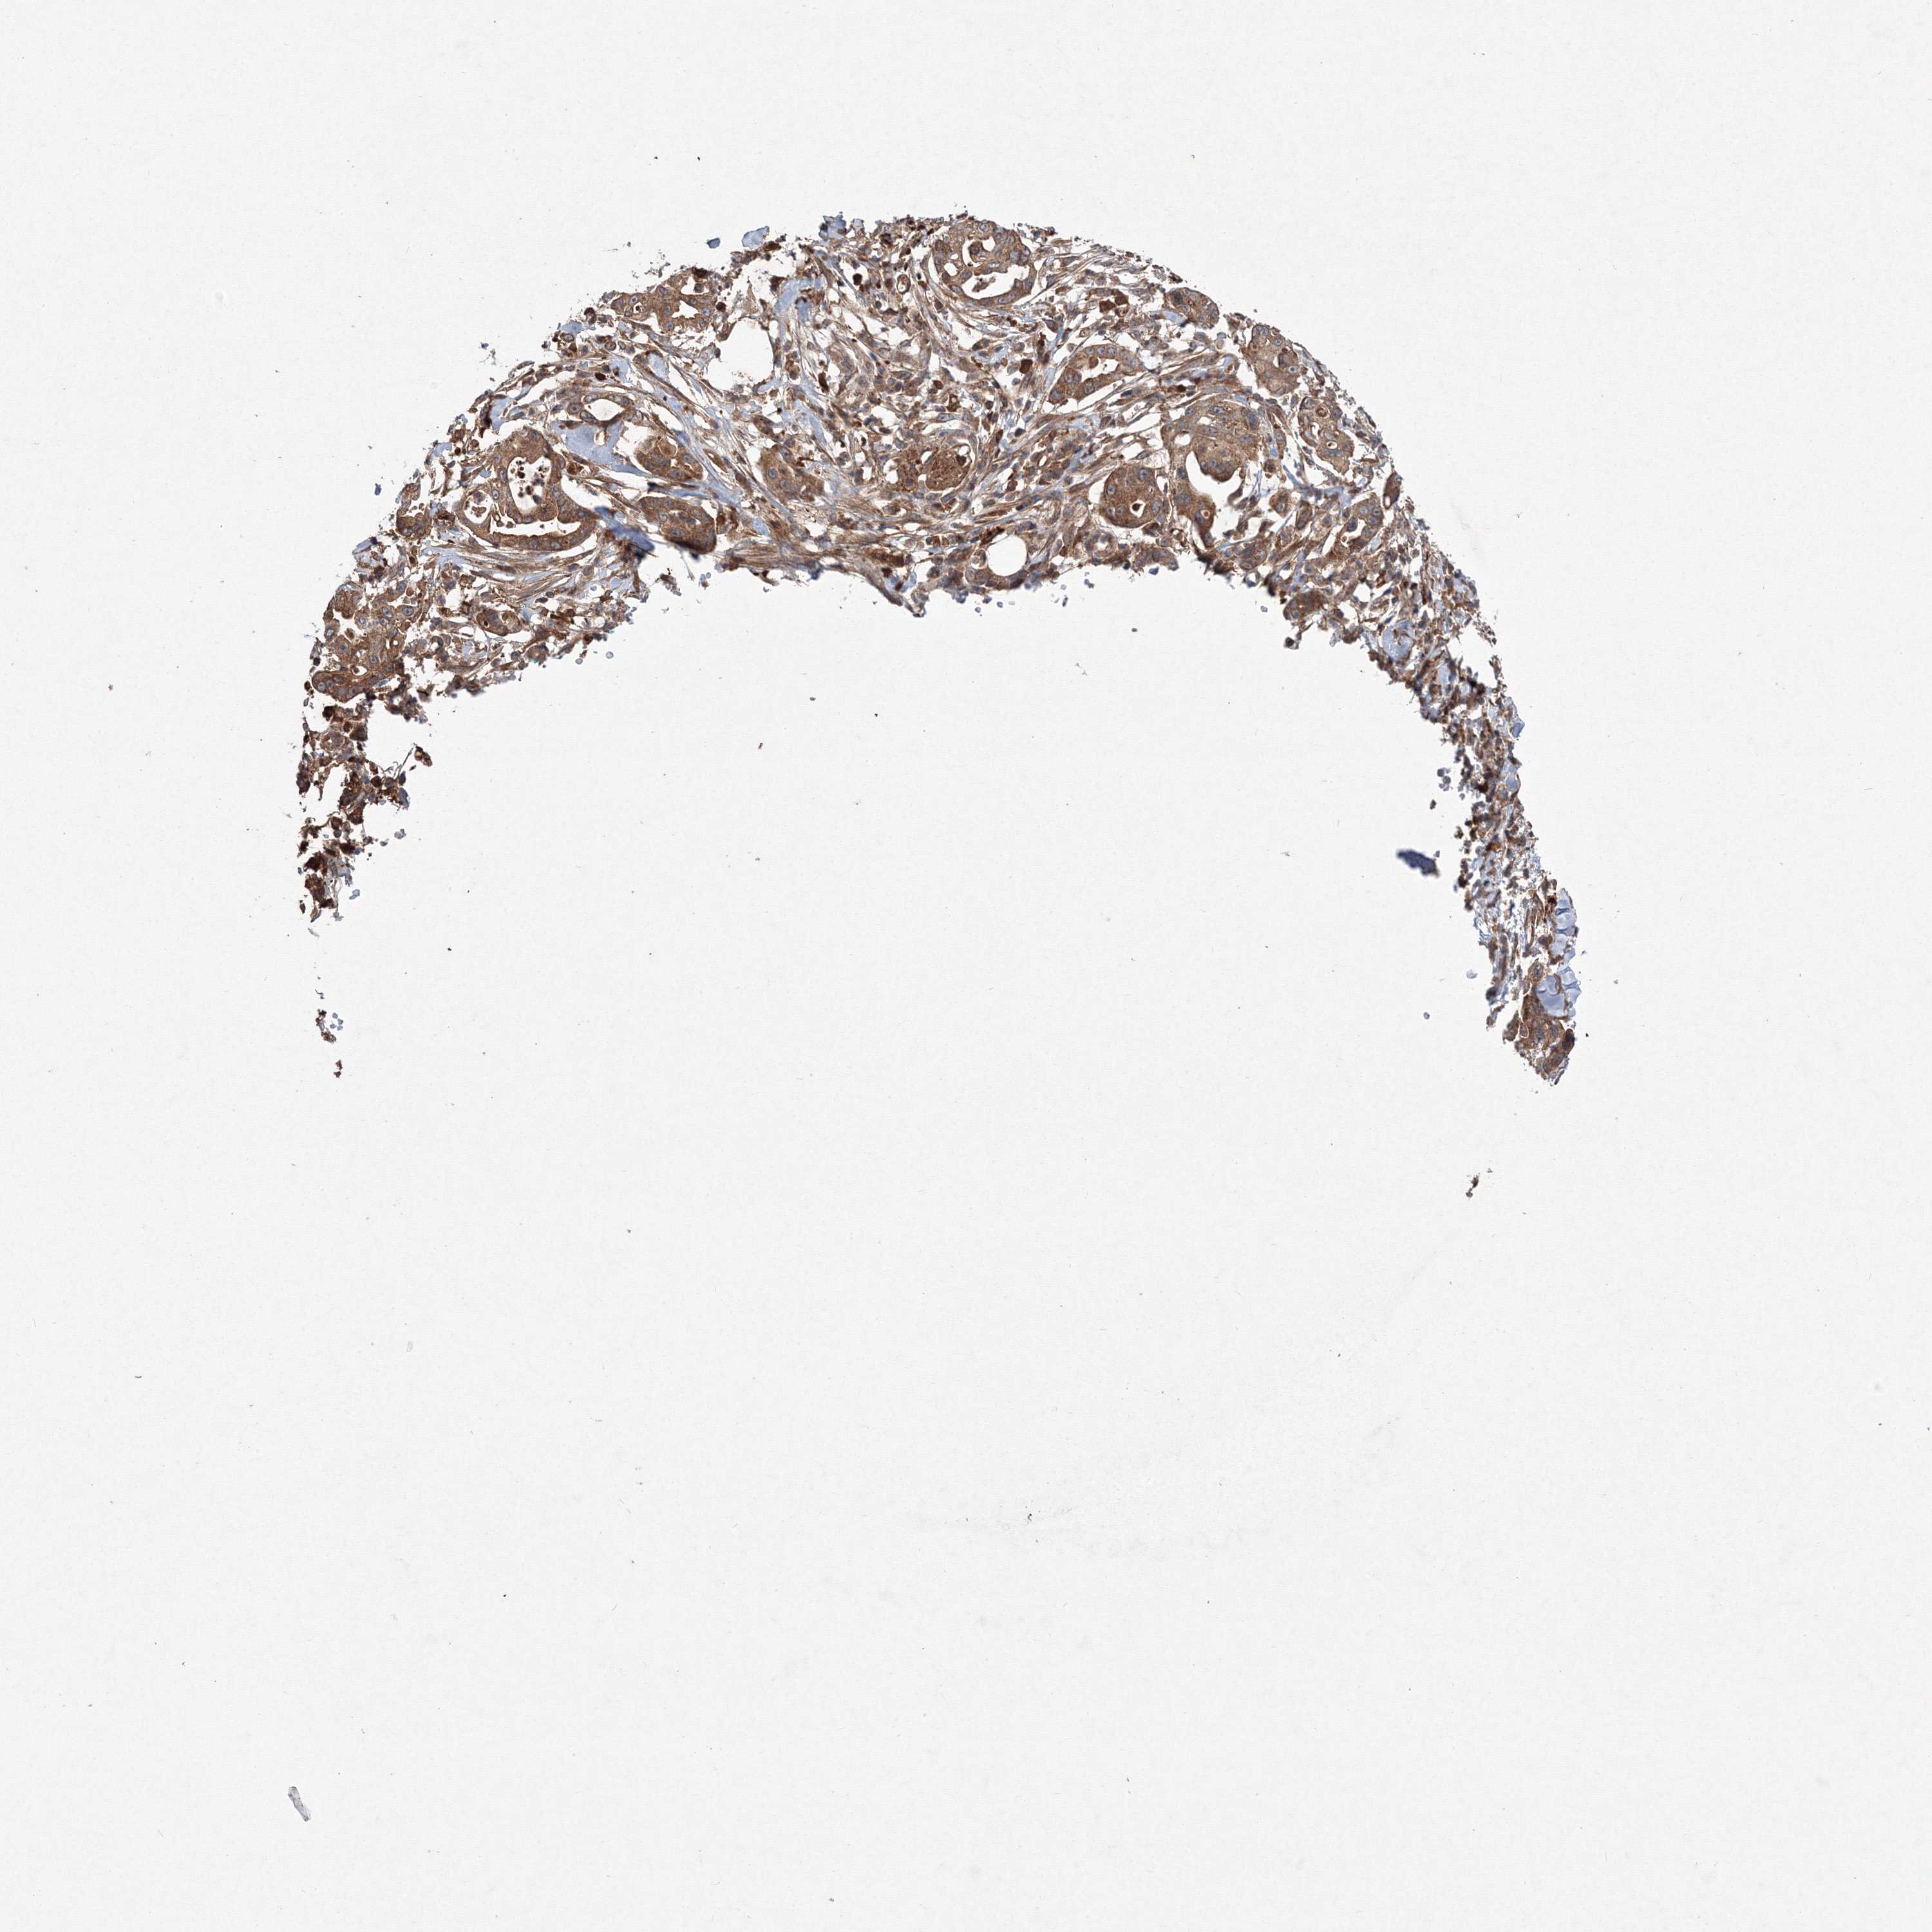

PANCREATIC CANCER - Protein expressioni

A mouse-over function shows sample information and annotation data. Click on an image to view it in a full screen mode. Samples can be filtered based on level of antibody staining by selecting one or several of the following categories: high, medium, low and not detected. The assay and annotation is described here.

Note that samples used for immunohistochemistry by the Human Protein Atlas do not correspond to samples in the TCGA dataset.

Antibody stainingi

Antibody staining in the annotated cell types in the current human tissue is reported as not detected, low, medium, or high, based on conventional immunohistochemistry profiling in selected tissues. This score is based on the combination of the staining intensity and fraction of stained cells.

Each image is clickable and will lead to virtual microscopy that enables deeper exploration of all samples and also displays staining intensity scores, fraction scores and subcellular localization as well as patient and tissue information for each sample.

Antibody HPA037471

Antibody HPA037472

Antibody HPA061526

Staining

High

Medium

Low

Not detected

Intensity

Strong

Moderate

Weak

Negative

Quantity

>75%

75%-25%

<25%

None

Location

Nuclear

Cytoplasmic/membranous

Cytoplasmic/membranous,nuclear

Adenocarcinoma, NOS